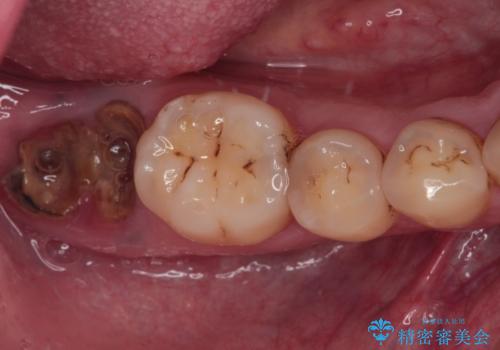

左上の犬歯が欠損しているため、正中の位置や奥歯の咬み合わせが理想的にならない点を了承していただきました。